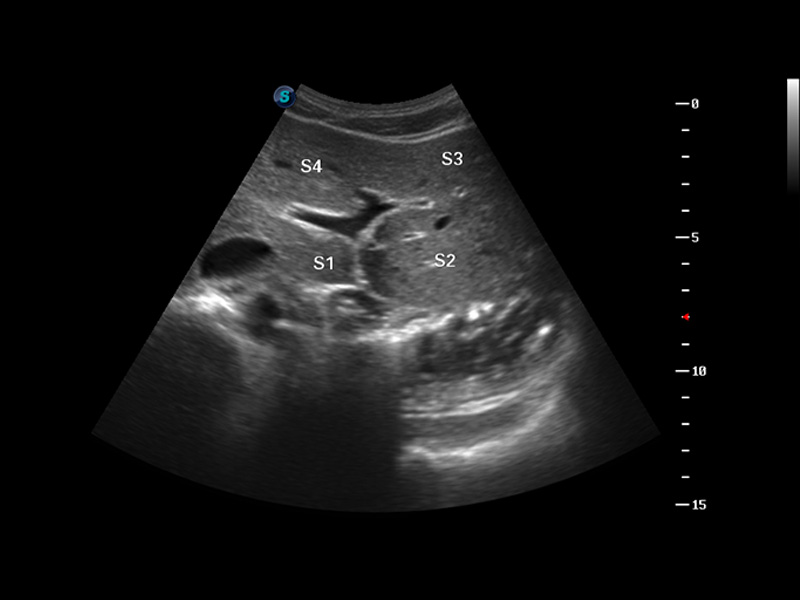

S8 EXP便携式彩色多普勒超声诊断仪是狗万官方网站研发的高端全身应用型便携彩超。高通道的VIS平台融合可视化(Visual)、智能化(Intelligent)和人性化(Smart)的特点,配以狗万官方网站自主研发生产的探头大家族,使您能够快速、准确的获得病人信息,提高工作效率的同时减轻疲劳。